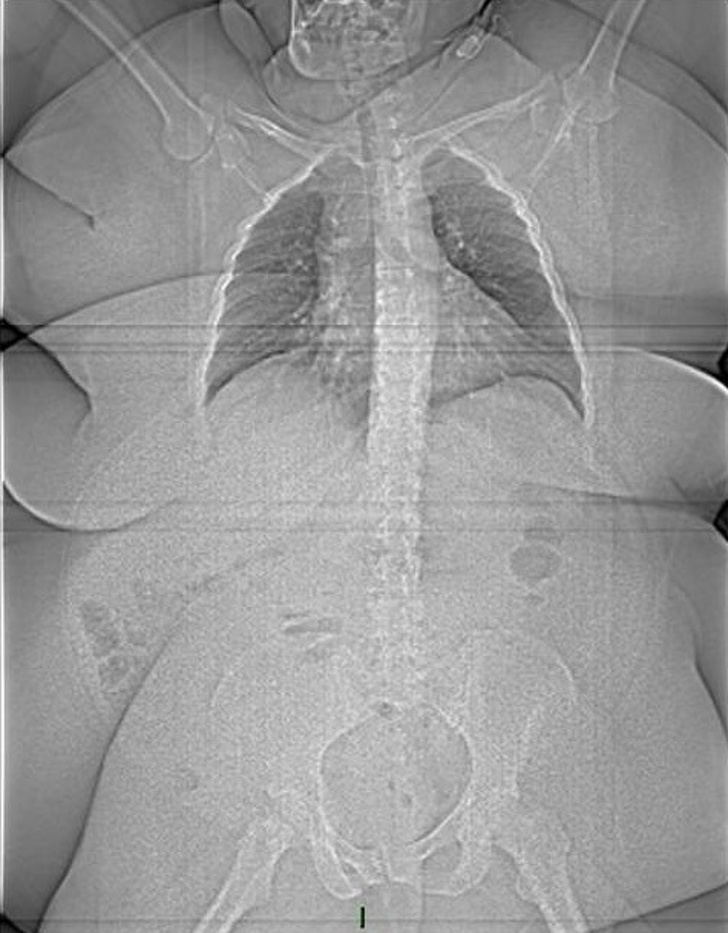

Egy 185 kilós felnőtt ember röntgenfelvétele. Jól látható, hogy a testét beborító zsírszövet kitakarja a csontokat.